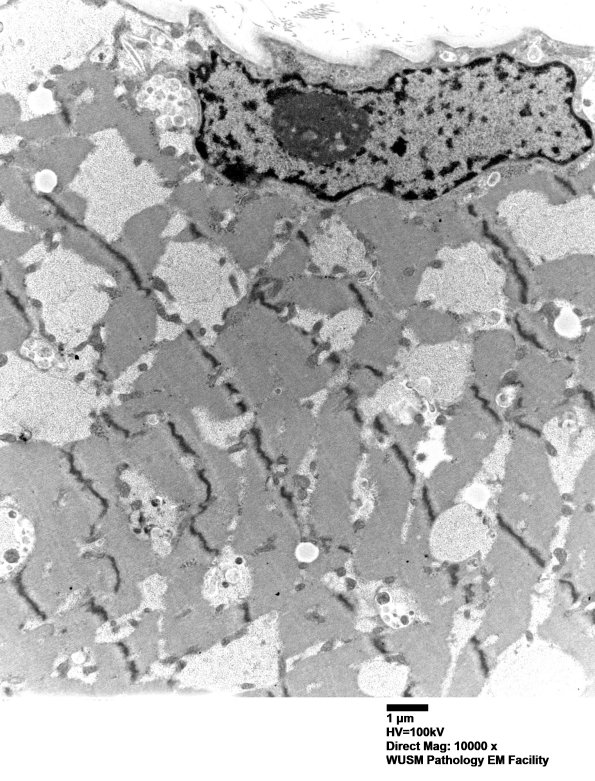

5D1-14 Examination by electron microscopy reveals abundant deposits of finely granular glycogen, both membrane-bound and free, interspersed throughout the myofiber and in subsarcolemmal locations. ---- 5D1,2 Low magnification ultrastructural images show the vacuoles contain granular material. (electron micrographs)